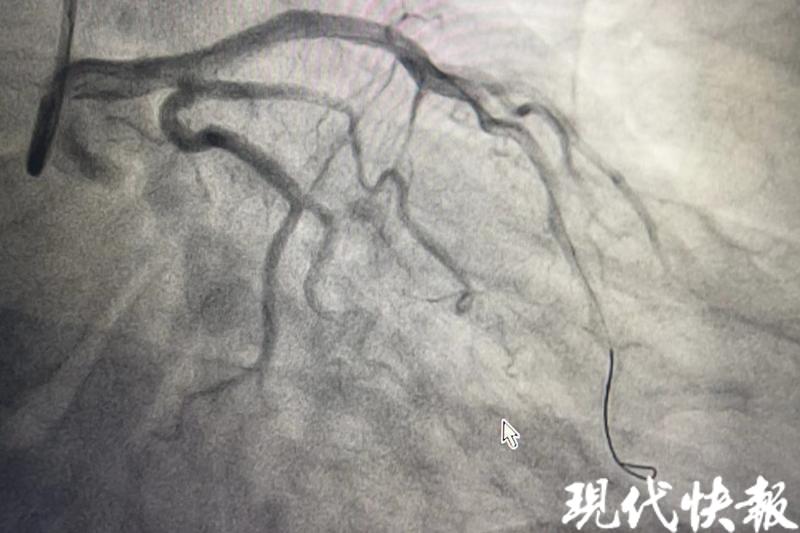

△患者心脏血管开通后

术中造影发现,张先生左前降支近段有85%至90%的狭窄,40分钟后,手术顺利结束,他安返病房。在医护人员的照护下,脱离生命危险。“患者才43岁,如果再迟点就医,有可能猝死,错失抢救的最佳时机。”曹松臻回忆。